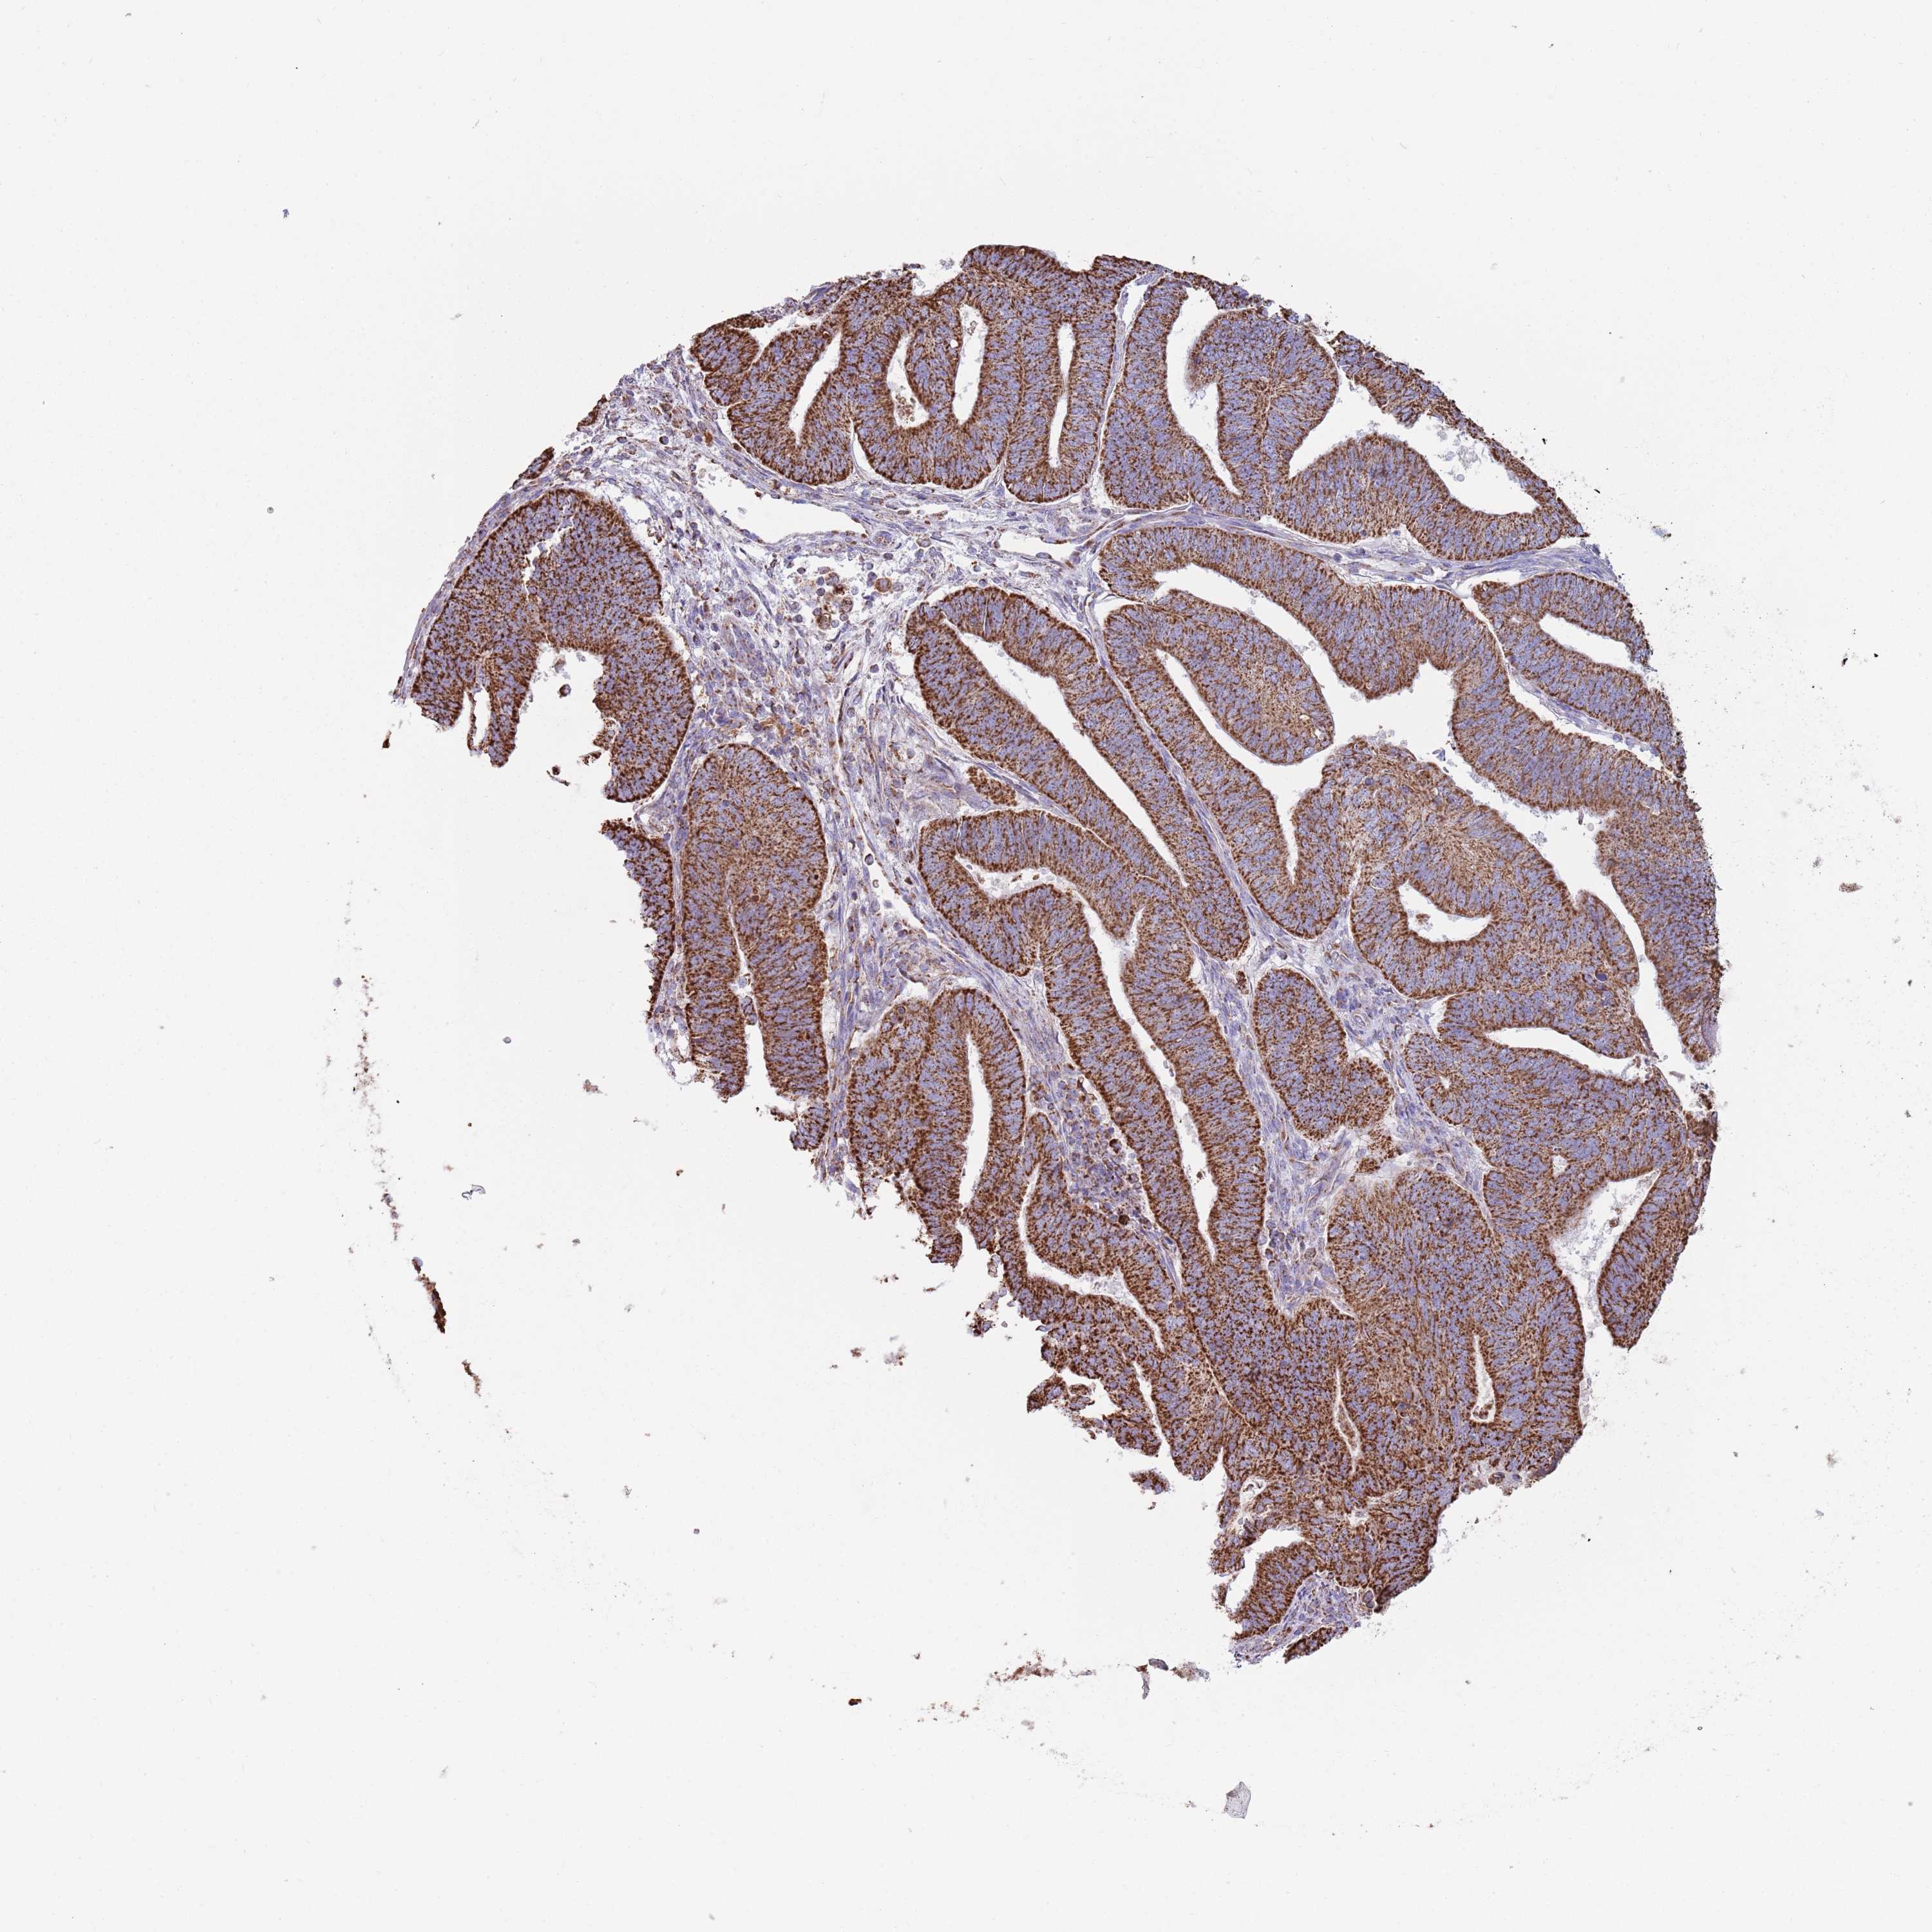

ENDOMETRIAL CANCER - Protein expressioni

A mouse-over function shows sample information and annotation data. Click on an image to view it in a full screen mode. Samples can be filtered based on level of antibody staining by selecting one or several of the following categories: high, medium, low and not detected. The assay and annotation is described here.

Note that samples used for immunohistochemistry by the Human Protein Atlas do not correspond to samples in the TCGA dataset.

Antibody stainingi

Antibody staining in the annotated cell types in the current human tissue is reported as not detected, low, medium, or high, based on conventional immunohistochemistry profiling in selected tissues. This score is based on the combination of the staining intensity and fraction of stained cells.

Each image is clickable and will lead to virtual microscopy that enables deeper exploration of all samples and also displays staining intensity scores, fraction scores and subcellular localization as well as patient and tissue information for each sample.

Antibody HPA048392

Staining

High

Medium

Low

Not detected

Intensity

Strong

Moderate

Weak

Negative

Quantity

>75%

75%-25%

<25%

None

Location

Nuclear

Cytoplasmic/membranous

Cytoplasmic/membranous,nuclear

Adenocarcinoma, NOS